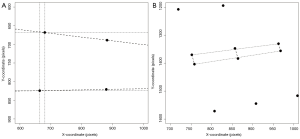

The Cobb’s kyphosis angle was calculated from the raw coordinates by the formula: α=β1+β2 = arctan(∆yI/∆xI) + arctan(∆yII/∆xII) = arctan[(y1–y2)/(x1–x2)] + arctan[(y3–y4)/(x3–x4)] (Figure 2). We computed the Pearson’s correlation coefficient r and corresponding t-test statistic between the calculations derived from the SpineAnalyzer® software and the manual measurements for the Cobb’s kyphosis angle. In addition, the intraclass correlation coefficient (two way mixed, consistency and agreement) with the matching F-test statistic was determined and classified according to Landis and Koch (20). Finally, we evaluated if the differences between measurements was different from 0 by a t-test and mapped the results in a Bland-Altman plot including calculation of the interval between the 95% limits of agreement by taking the mean difference plus and minus 2 standard deviations (21) to further evaluate the agreement between the measurements. SPSS statistics software version 20 (IBM, Armonk, NY, USA) and R software version 3.0.1 (R Foundation for Statistical Computing, Vienna, Austria) were used for the analyses.

The mean kyphosis angle between the superior endplate of Th5 and the inferior endplate of Th12 of the sample as determined by the SpineAnalyzer® software measurements was 53° with a standard deviation of 10° and the mean kyphosis angle by manual measurements was 54° with a standard deviation of 12°. The Pearson’s correlation coefficient r between the manual measurements and the calculations derived from the SpineAnalyzer® software was 0.65 [95% confidence interval (CI): 0.53-0.75; P=2×10–13] (Figure 3). There was a substantial intraclass correlation with a coefficient of 0.64 for both consistency and absolute agreement (95% CI: 0.51-0.74 P=5×10–13 and P=4×10–13, respectively). The mean difference between methods was 1° (95% CI: –2°-4°) and not different from 0 (P=0.4). The interval between the 95% limits of agreement was –20°-17° where approximately half the individuals (47%) showed a difference of less than 5° and about three quarters less than 10° between the techniques (76%). The Bland-Altman plot did not show systematic biases of proportional error, dependency of variation on the magnitude of measurements, extreme outliers, systematic under- or overestimation (Figure 4).